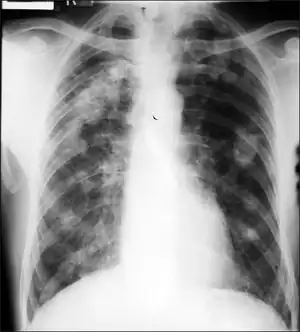

Caplan's syndrome (or Caplan disease or rheumatoid pneumoconiosis[1]) is a combination of rheumatoid arthritis (RA) and pneumoconiosis that manifests as intrapulmonary nodules, which appear homogeneous and well-defined on chest X-ray.[2]

Caplan syndrome is a nodular condition of the lung occurring in dust-exposed persons with either a history of rheumatoid arthritis (RA) or who subsequently develop RA within the following 5–10 years.[3] The nodules in the lung typically occur bilaterally and peripherally, on a background of simple coal workers' pneumoconiosis. There are usually multiple nodules, varying in size from 0.5 to 5.0 cm. The nodules typically appear rapidly, often in only a few weeks. Nodules may grow, remain unchanged in size, resolve, or disappear and then reappear. They can cavitate, calcify, or develop air-fluid levels. Grossly, they can resemble a giant silicotic nodule. Histologically, they usually have a necrotic center surrounded by a zone of plasma cells and lymphocytes, and often with a peripheral inflammatory zone made of macrophages and neutrophils.

- Chest radiology shows multiple, round, well defined nodules, usually 0.5-2.0 cm in diameter, which may cavitate and resemble tuberculosis.